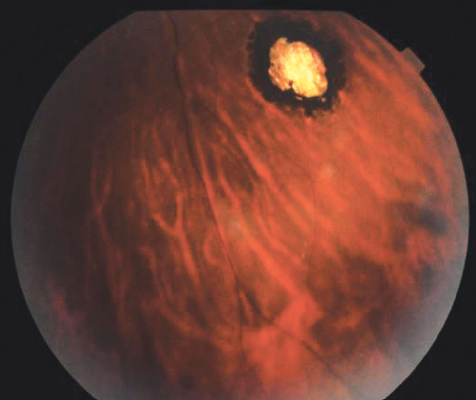

Объективно: ОD — передний отдел без патологии. Оптические среды прозрачные. В стекловидном теле (СТ) большое количество клеточных элементов, плавающих помутнений. Глазное дно под «густым флёром», ДЗН с нечёткими границами, по ходу сосудистого пучка просматривается фокус размером около 2,5 PD, неправильной формы с нечёткими границами, проминирующий в СТ, желтоватого цвета, сетчатка вокруг инфильтрирована, сосуды полнокровны, макулярный рефлекс размыт, просматриваются единичные ретинальные геморрагии (рис. 1). На периферии несколько хориоретинальных очагов с чёткими границами, грубо пигментированные (рис. 2, 3). ОS — передний отдел без патологии. Неравномерная конденсация фибрилл СТ. Глазное дно: ДЗН розовый, контуры чёткие, на периферии грубый хориоретинальный очаг с пигментом, размером менее 1,0 PD и три плоских небольших пигментированных очага.

Рис. 1. Фотография глазного дна правого глаза пациентки. Парацентральный очаговый хориоретинит в стадии инфильтрации. Периферический очаговый хориоретинит в рубцовой стадии / Fig. 1. Fundus photography of the right eye of a patient. Paracentral focal chorioretinitis in the infiltration stage. Peripheral focal chorioretinitis in the cicatricial stage